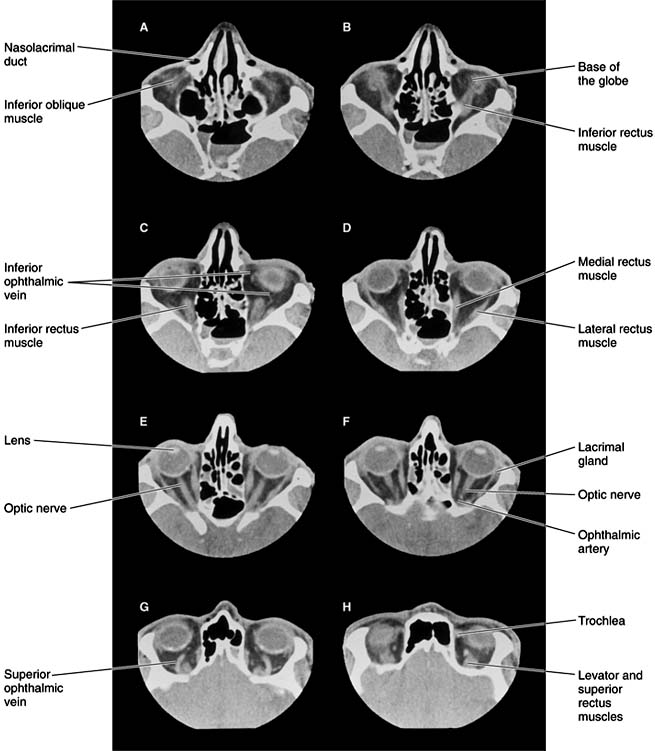

Figure 13-1

Figure 13-1: Normal CT scan showing the anatomy of the orbit. Axial CT sections, thickness 1.5 mm. A: Lowest section. H: Highest section. Note clear delineation of individual muscles, optic nerve, and major veins within the orbital fat.